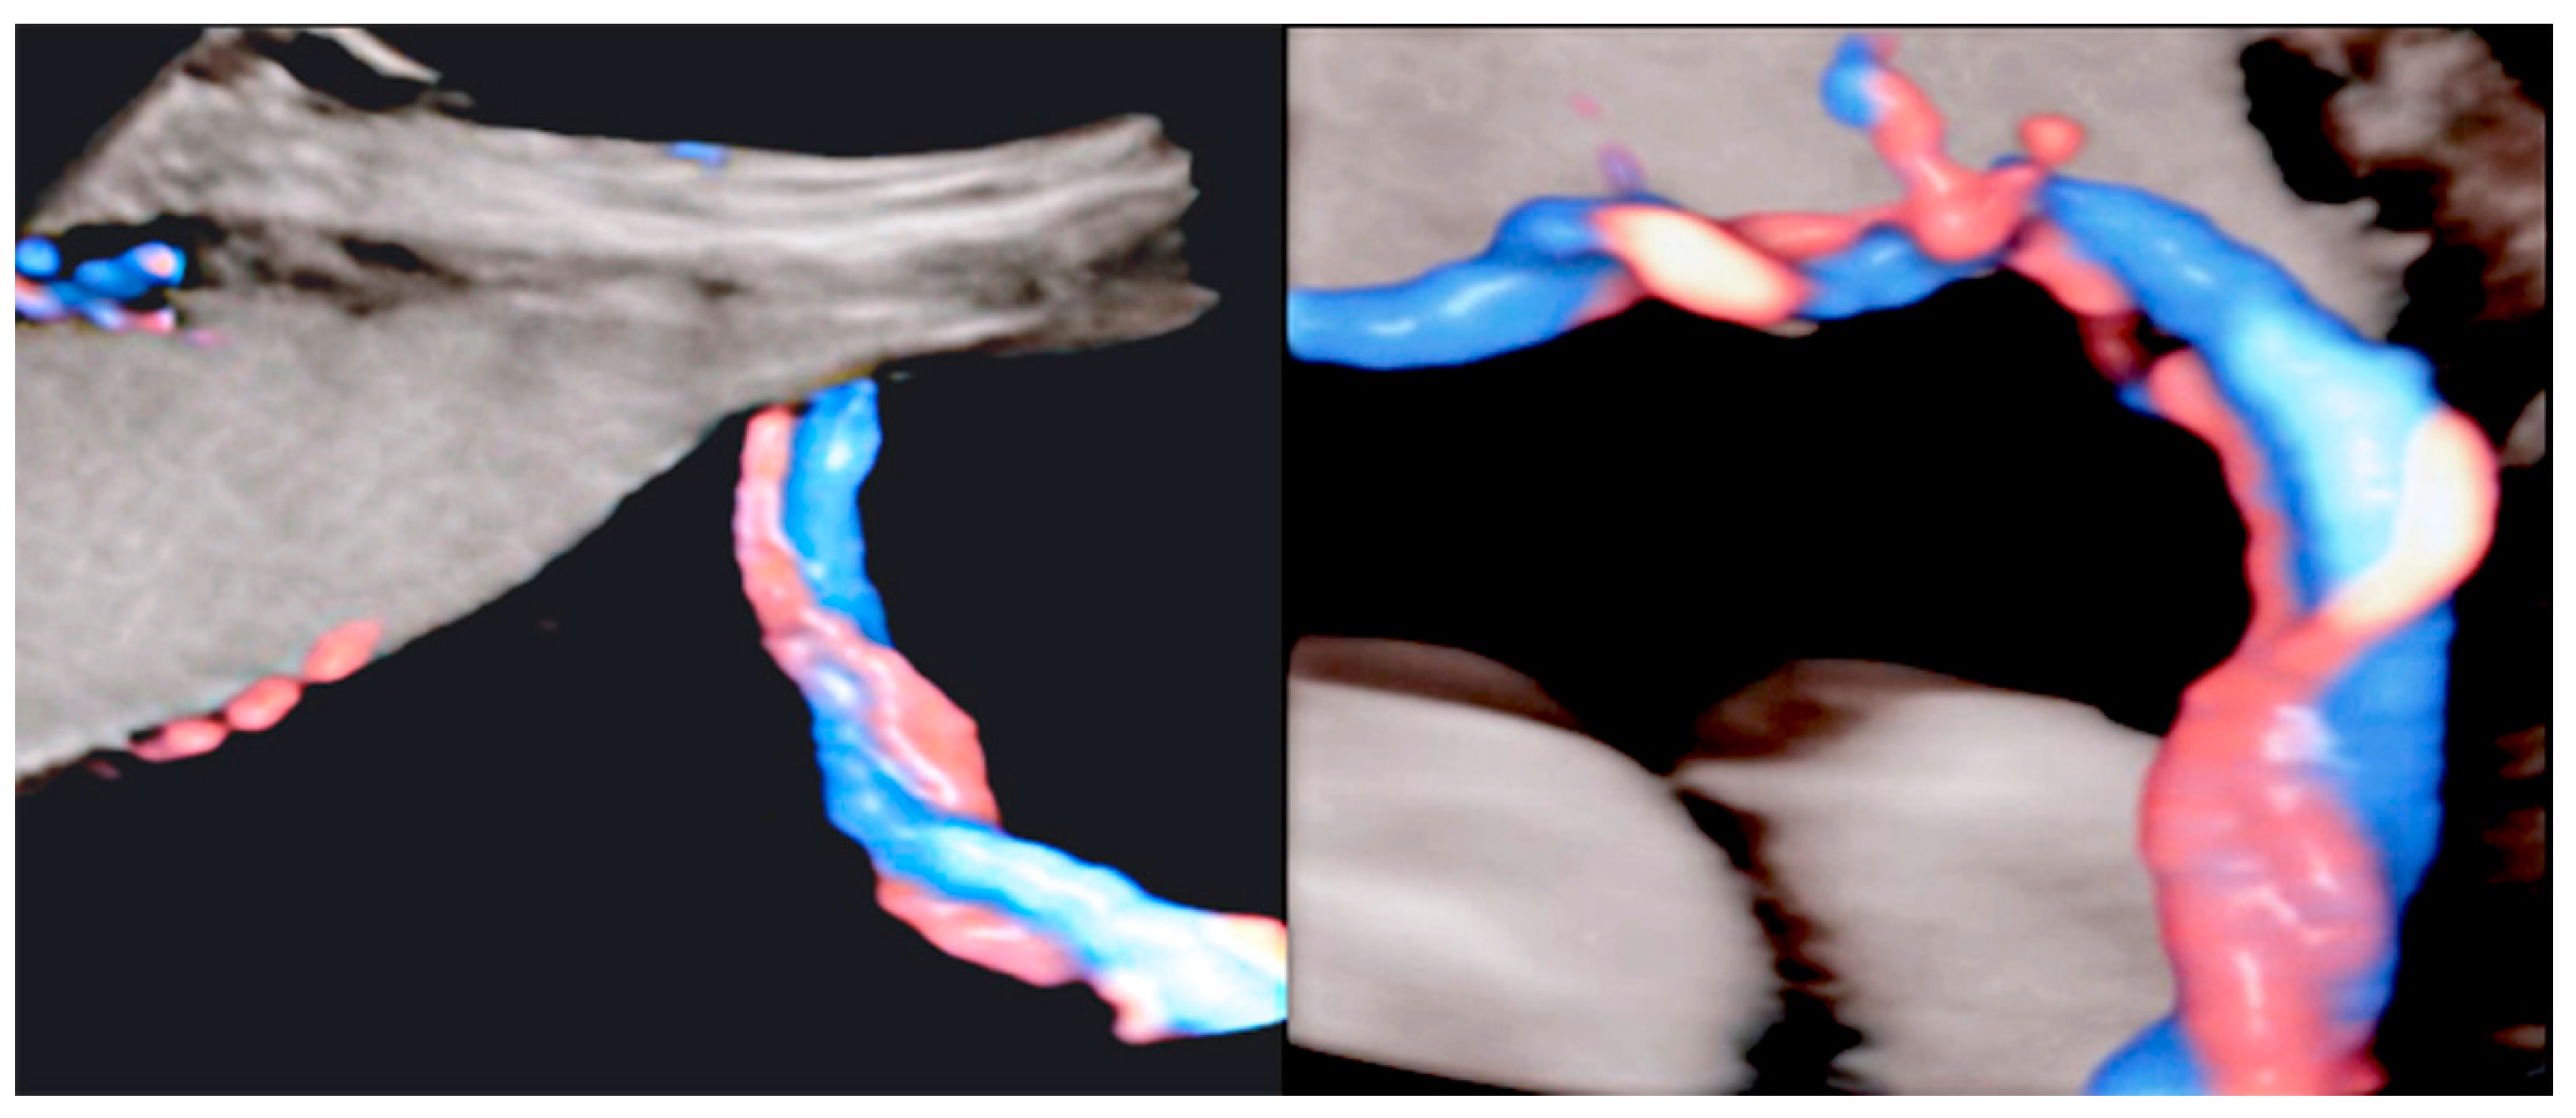

3.2.6. Umbilical Cord Entanglement

3.2.7. Umbilical Cord Hemangioma